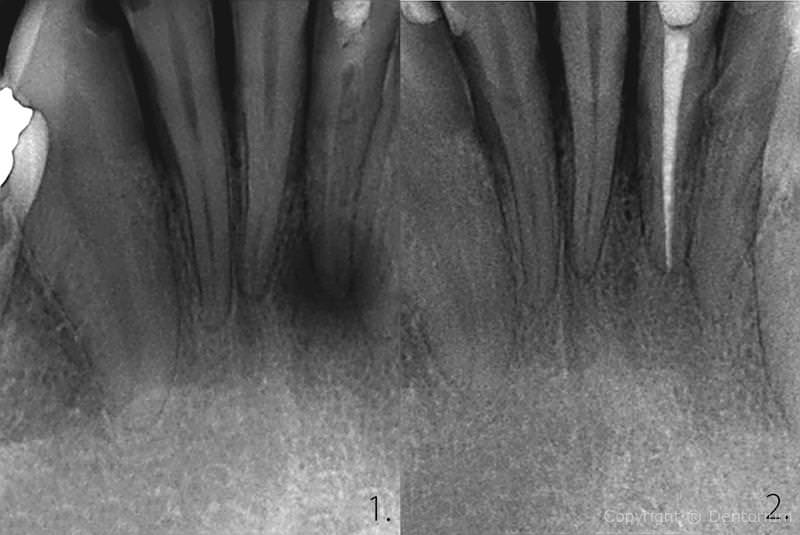

Il trattamento endodontico o trattamento canalare è necessario quando la polpa dentale è danneggiata dalle infezioni batteriche dalla carie o da trauma del dente.

- pulizia, allargamento e disinfezione del canale, somministrazione della medicina

- l’estrazione della medicina dentale, otturazione dei canali radicolari

Immediamente dopo il trattameneto si procede con RVG controllo del canale trattato.